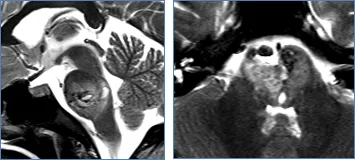

巴教授根据桥脑的解剖及病变的复杂关系总结了五大手术入路,包括:经髓帆入路、经桥脑臂入路、远外侧入路、小脑上外侧入路、颞下经天幕入路。具体的手术入路要根据每个患者的具体情况及主刀医生的医学知识及经验而具体制定。

远外侧入路示意图,脑干安全进入区:延髓脑桥沟区域